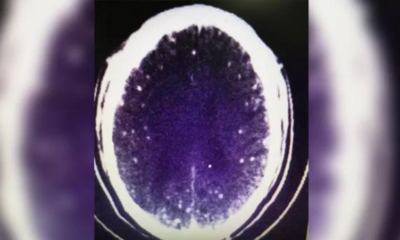

Градежен работник од Кина на возраст од 46 години доживеал напади по јадењето супа од свинско и овчо месо, а подоцна било откриено дека има црви...